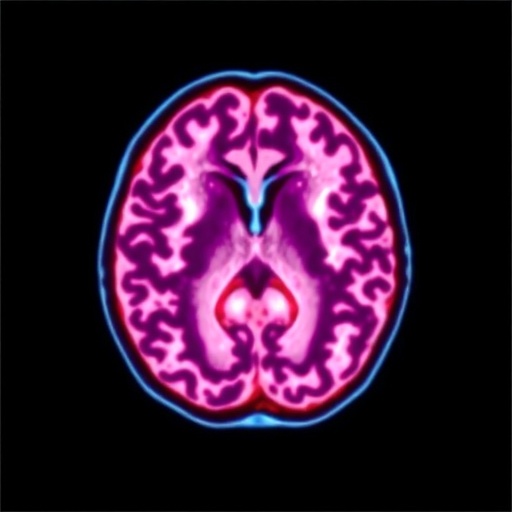

Strikingly, the combination therapy group demonstrated significantly enhanced neurological recovery compared to the control cohort, with a higher proportion achieving favorable mRS scores indicative of functional independence. This improvement correlated with a measurable decrease in ischemic core expansion on follow-up neuroimaging, suggesting albumin’s efficacy in curtailing secondary injury cascades triggered by reperfusion. The researchers hypothesize that albumin’s antioxidant and anti-inflammatory effects attenuate microvascular damage and cerebral edema, mechanisms that complement mechanical restoration of blood flow. These results underscore the therapeutic value of targeting both vascular occlusion and the downstream neurobiological processes in stroke management.